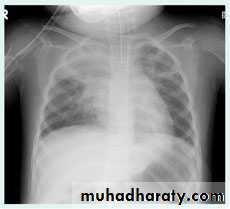

Radiographic features

Consolidated areas are radio opaque on chest radiograph and chest CT compared to normally air filled lung tissue.

Lobar consolidation

Where increased density/opacity is seen in individual lung lobes. Sharp delineation can be seen when consolidation reaches a fissure, since it does not cross. Air bronchograms can also be seen due to bronchi becoming visible against the dense diseased tissue. Volume loss is usually not seen..